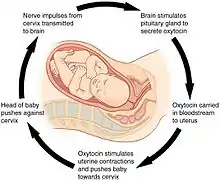

Psychological

During the later stages of gestation there is an increase in abundance of oxytocin, a hormone that is known to evoke feelings of contentment, reductions in anxiety, and feelings of calmness and security around the mate.[25] Oxytocin is further released during labour when the fetus stimulates the cervix and vagina, and it is believed that it plays a major role in the bonding of a mother to her infant and in the establishment of maternal behaviour. Studies show that the father of the child also has an increase in oxytocin levels following contact with the infant and parents with higher oxytocin levels showed more responsiveness and synchrony in their interactions with their infant. The act of nursing a child also causes a release of oxytocin to help the baby get milk more easily from the nipple.[26][27]

Augmentation

Augmentation is the process of stimulating the uterus to increase the intensity and duration of contractions after labour has begun. Several methods of augmentation are commonly been used to treat slow progress of labour (dystocia) when uterine contractions are assessed to be too weak. Oxytocin is the most common method used to increase the rate of vaginal delivery.[106] The World Health Organization recommends its use either alone or with amniotomy (rupture of the amniotic membrane) but advises that it must be used only after it has been correctly confirmed that labour is not proceeding properly if harm is to be avoided. The WHO does not recommend the use of antispasmodic agents for prevention of delay in labour.[107]